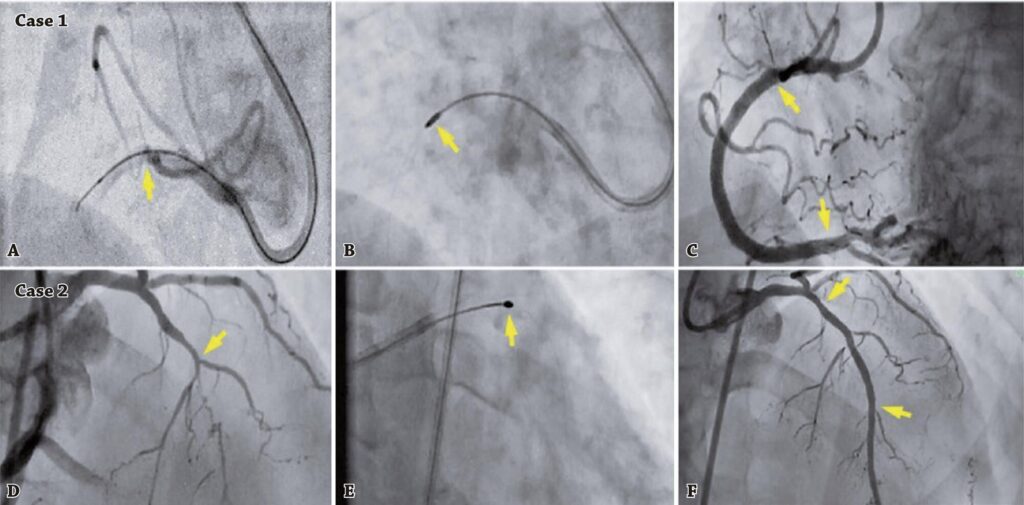

How to cross the uncrossable lesions in chronic total occlusion

Coronary chronic total occlusion occurred in approximately 15 to 20% of patients. The most common challenges associated with successful percutaneous coronary intervention in chronic total occlusion are undilatable and uncrossable lesions. Uncrossable lesions are characterized as those lesions in which the balloon cannot cross the lesion. These types of lesions are commonly seen in calcified and tortuous arteries, and in chronic total occlusion. Various techniques, such as side branch anchoring, rotational, orbital, or laser atherectomy can be used to treat these challenging lesions. In this article, we describe the tips and tricks which can be commonly used to cross uncrossable lesions.